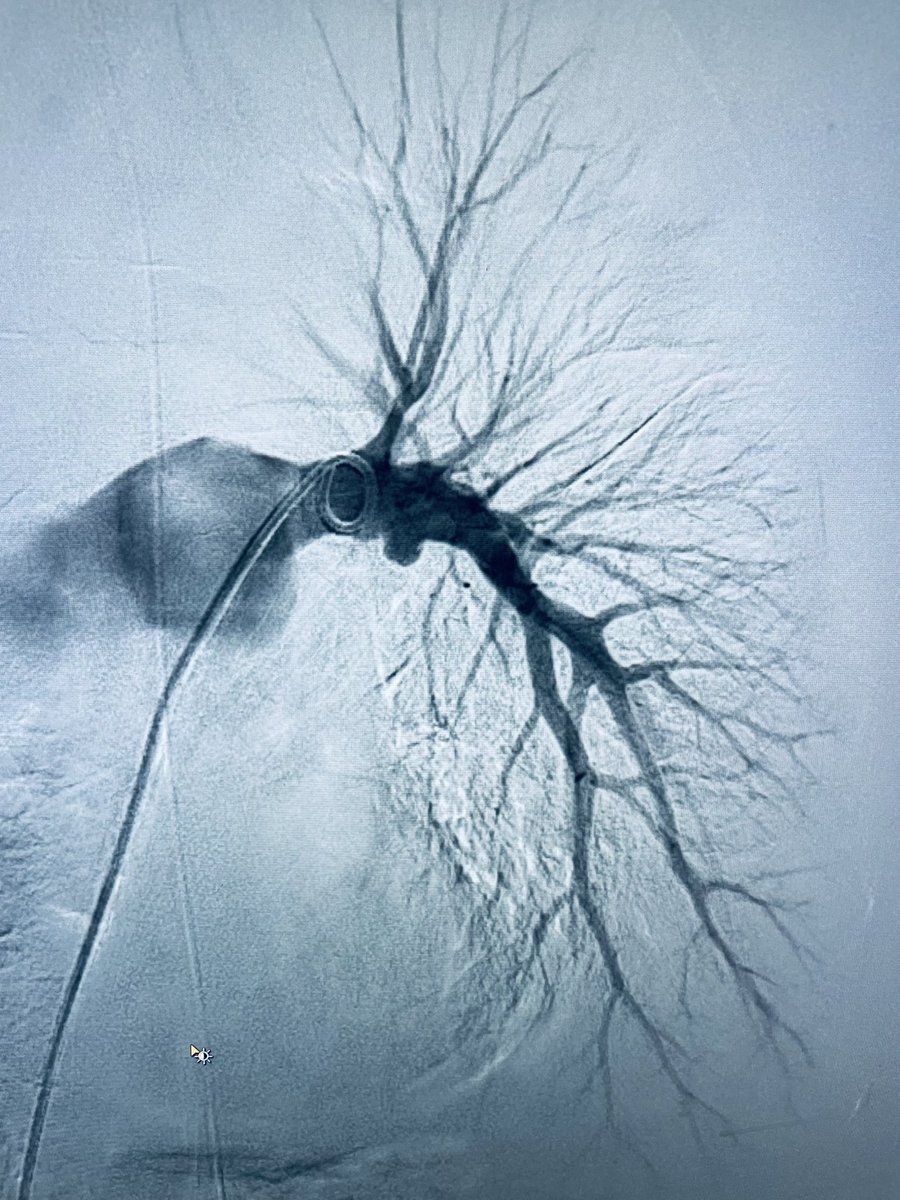

New study @AnnalsofIM bit.ly/2Km3KYu by @DrTalenfeld @WeillCornell: Percutaneous ablation for T1a #renalcancer has similar 5-year survival rates to radical nephrectomy but with far fewer 30-day complications and less #kidneyfailure.